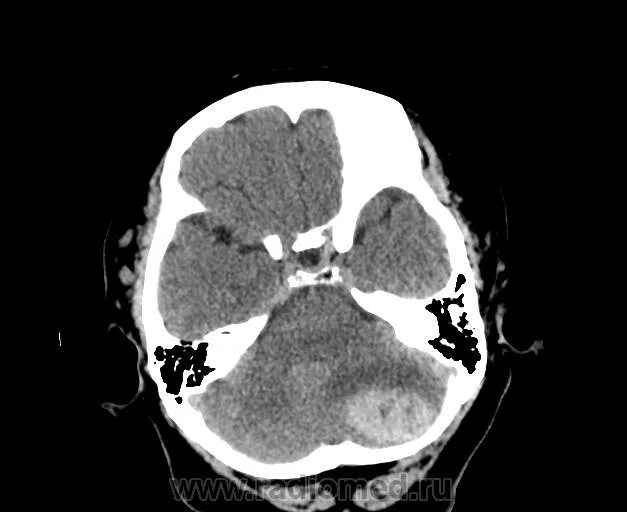

Отек мозга метастазы